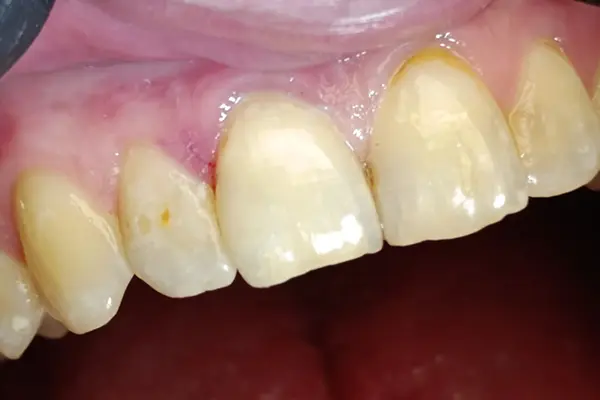

В данном клиническом случаем от Виталия Семёновича Лаврысь мы рассмотрим лечение кариеса дентина зуба 1.1 (класс III, Black) использованием композитов B&E. Эмаль вестибулярной стенки предельно тонкая, без дентинной поддержки. Визуализируется большой участок деминерализации эмали.

Перевели полость в сквозной дефект. Для упрощения построения дистальной стенки оставлен участок эмали без дентинной поддержки.